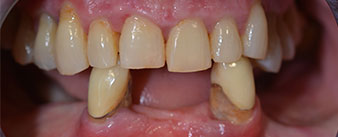

The 64-year-old patient presented with residual dentition of teeth 38, 33 and 43 and a clasp denture in the mandible (Fig. 1 and 2).

residual dentition

The necessary periodontal treatment and extraction in the maxilla was to be performed at a later point in time, as the patient is a teacher and was busy with school leaving exams at the time. She could neither eat nor speak properly, as the temporary prosthesis was very fragile, breaking regularly and under the slightest strain.

Following an explanation of the various treatment options open to her, the patient decided on extraction of the residual dentition in the mandible, an immediate implantation and treatment with the Fast & Fixed method (bredent medical), whereby the provisional fixed denture is screwed onto four implants on the same day as the surgery. The goal was to operate on the patient on the Friday so that she could assist in the oral examinations on the following Monday.